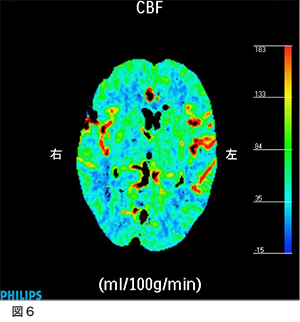

術後MRA、脳血管造影 図5

右は術後のMRAですが、術前ほとんど写っていなかった右中大脳動脈がバイパスからの血流で描出されるようになっています。左は、脳血管造影(右外頸動脈撮影)ですが、浅側頭動脈から中大脳動脈全域が描出されています。